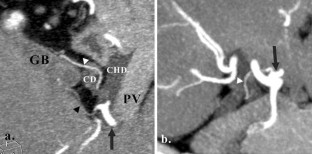

Assessment and classification of cystic arteries with 64-detector row computed tomography before laparoscopic cholecystectomy

Major complications of laparoscopic cholecystectomy are bleeding and bile duct injury, and it is necessary to clearly identify structures endoscopically to keep bleeding and injury from occurring. The aim of this study was to depict the anatomical variation between cystic arteries among patients using 64-detector row spiral computed tomography (CT) prior to laparoscopic cholecystectomy.

A total of 78 patients (31 men, 47 women) who underwent cholecystectomy were examined preoperatively using 64-detector row spiral CT between April 2012 and June 2013. The origin and number of cystic arteries and their relationship with the Calot triangle was evaluated by two independent observers. CT images were compared with laparoscopic cholecystectomy results.

The cystic arteries were delineated by CT in 73 of the 78 patients. The relationship between the cystic arteries and the Calot triangle was identified in 71 of the 78 patients. One cystic artery was found in 53 (73 %) of the 73 patients, while two cystic arteries were found in 20 (27 %) of the patients. A total of 55 (60 %) of the 91 cystic arteries passed through the Calot triangle. The remaining 36 cystic arteries (40 %) passed anterior, posterior, or inferior to the cystic duct. The relationship between the cystic arteries and the Calot triangle detected by CT was in agreement with the surgical records for all patients.

The configuration of the cystic arteries and their relationship with the Calot triangle can be identified using 64-detector row CT before laparoscopic cholecystectomy.